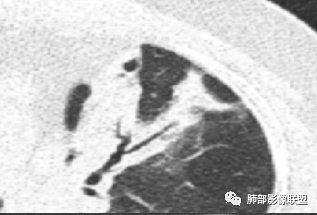

若晗: 结节十树芽十树雾

青藤之凉: 支原体肺炎的影像特征相对比较明显。有支气管壁增厚、支气管扩张样改变、支气管充气征。小叶小结节,有点状或者斑片状的浸润影、有实变影,表现为树芽征、树雾气征。

影像学特点:①支气管壁增厚、支气管周围炎。②腺泡结节、树芽征、树雾征(见病例1)。③结节融合,大片实变,部分边缘收缩。④分布上较广泛 。